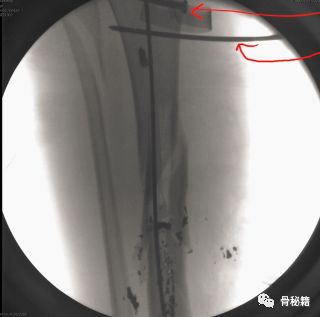

轻微粉碎的病例,多发伤患者,皮肤条件不好,不敢切开,先植入两枚阻挡钉,后方一个,侧方一个,进针之后,发现导针穿出后方……

说明这后方的阻挡钉没设计好,然后又在下方植入了一个阻挡克氏针